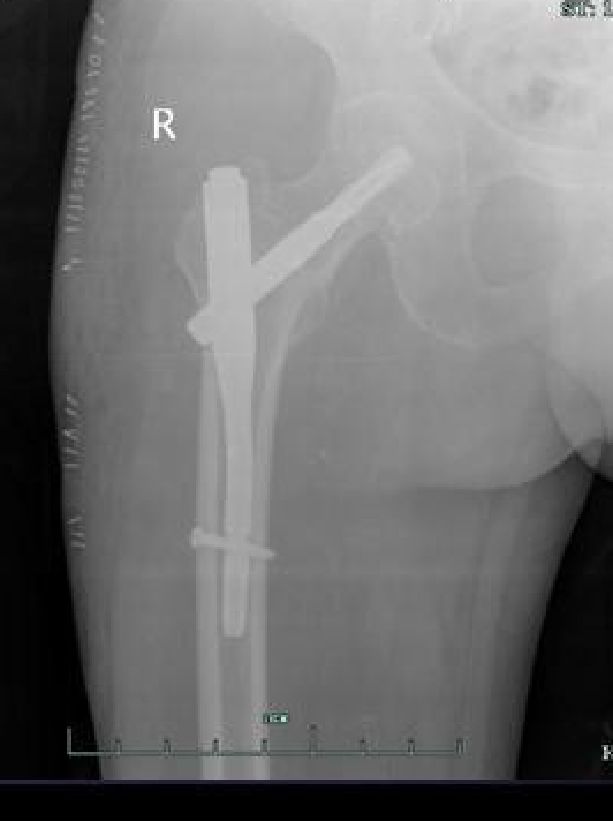

交锁髓内钉有较好的抗旋转、抗压缩作用,固定稳定性好,符合生物学固定原则(BO),在四肢长骨中应用广泛。

股骨粗隆下2cm距膝关节9cm以上的各种类型骨折。

固定骨折的力臂比钢板长,作用力均匀分散在整个骨干的中轴上,不易发生折弯变形。

锁钉使骨干从上到下形成一体,防止缩短和旋转,对骨折的固定达到最大的稳定性。

对于不稳定骨折,髓内固定的力学性能更好,力臂更短,术后器械相关并发症如股骨头切割、髋内翻、短缩和内固定物松动断裂概率更低。